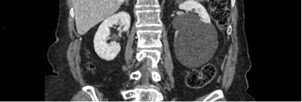

L’analyse des coupes abdominales montre également les images suivantes :

Question 5 - L’aspect évoque (une ou plusieurs réponses exactes) :

Formation transparenchymateuse rénale de densité liquidienne pure au temps portal, sans cloison, paroi épaisse, nodule pariétal ni calcification = kyste rénal simple. Pas de surveillance.

Les kystes rénaux sont très fréquents (50 % des patients après 50 ans), la plupart du temps découvert fortuitement, asymptomatiques, et bénins comme celui-ci.